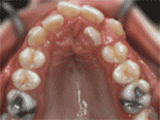

症状表现:牙齿缺失、牙周疾病等导致相邻牙齿无秩序前突。

症状表现:超出正常牙齿颗数,造成牙齿排列不齐,一般需要拔牙。

症状表现:牙齿过多,牙槽骨过窄,使牙齿没有足够空间生长就会造成牙齿排列不齐,需根据情况判断是否拔牙。

症状表现:通俗来讲就是咬牙时无法紧闭,上下牙齿中间有缝。

症状表现:上牙边沿覆盖下牙超过1/3,俗话说的天包地。

症状表现:疾病外因等造成的牙列稀疏,牙槽骨过长或牙齿缺失,导致排列太宽松,零零散散。

症状表现:下牙边沿覆盖上牙超过1/3,俗话说的地包天。